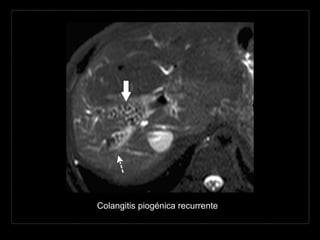

Hallazgos por TC

• cálculos hiperdensos o isodensos al hígado

• + C

• dilatación biliar intra- y extrahepática*

• dilatación del colédoco

• disminución del calibre abrupta en “cabeza de flecha”

• abscesos hepáticos (20%)

• neumobilia*

• atrofia grasa de segmentos hepáticos.

Hallazgos por RM

• T1: dilatación biliar hipointensa + cálculos de

intensidad intermedia (anillo hiperintenso)

• T2: bilis hiperintensa con cálculos hipointensos

• T1 + C: dilatación biliar hipointensa + cálculos de

• CPRM: dilatación intra- y extrahepática con

defectos de llenado representando cálculos.